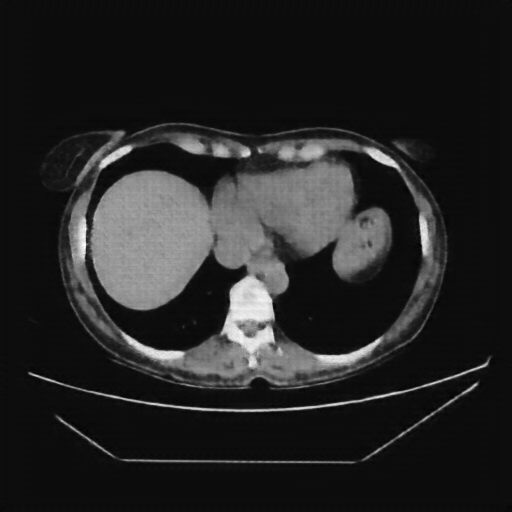

Reconstructed NATIVE CT scan (cycle consistency)

Full window (WL 1023.5, WW 4095 β†’ Low βˆ’1024, High +3071)

Actual HU range: [-832.9, 629.2]